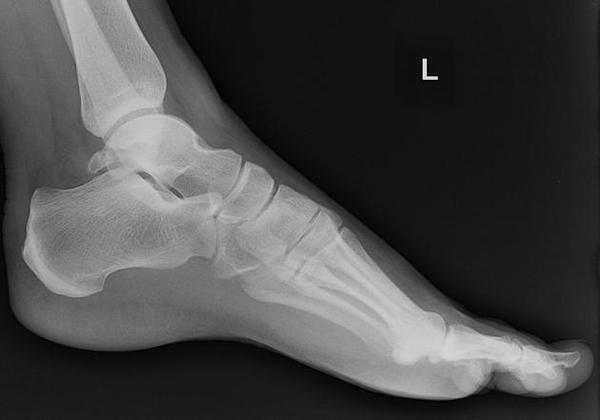

6. What is this finding on x-ray?

Correct Answer: Os trigonum

The os trigonum is a small, accessory bone located at the back of the talus (a bone in the ankle). It forms when a secondary ossification center in the talus fails to fuse during development. While often asymptomatic, it can sometimes cause pain and impingement in the ankle, especially in athletes or dancers, a condition known as os trigonum syndrome. This is also called "nutcracker phenomenon"